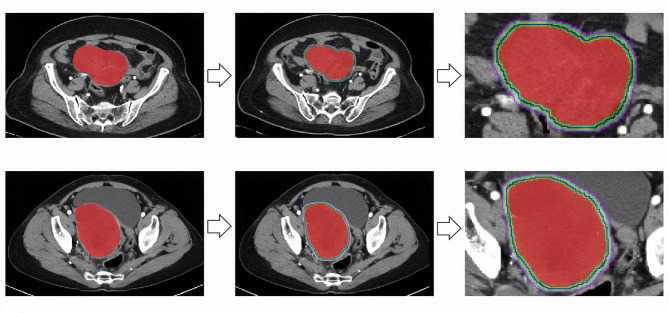

Methods: This retrospective cohort analysis involved 273 participants from Qingdao University Affiliated Hospital and Rizhao People's Hospital, and they were categorized into the training, testing, and external validation groups. Imaging characteristics were derived from the tumor region of interest and its surrounding areas (1-5 mm), and radiomics scores were calculated for each region. This approach was employed for assessing the diagnostic performance of different regions and identify the optimal one. We constructed a risk prediction model that integrated imaging features of the optimal region with independent clinical risk factors.